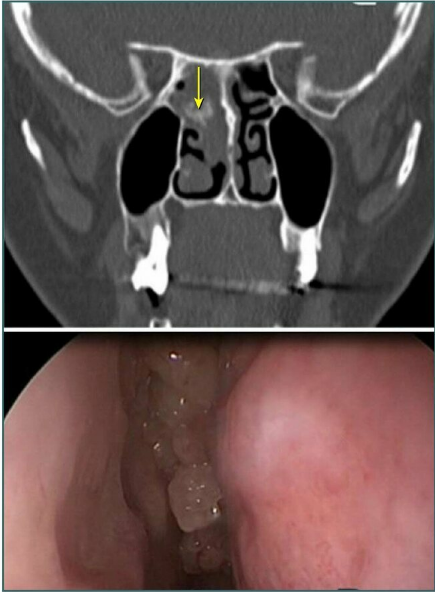

Fossa of Rosenmuller (yellow arrow) is visualized during the _____ pass of diagnostic nasal endoscopy.